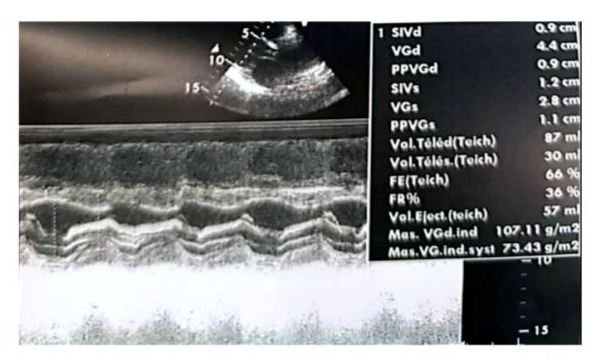

We report the case of a 70-year-old female patient with a history of poorly controlled arterial hypertension, presenting with two coexisting conditions that required either a two-step approach or simultaneous management, involving a thyroidectomy followed by cardiac surgery under cardiopulmonary bypass (CPB). In our case, a simultaneous approach was chosen following a multidisciplinary consultation. With a medical history of poorly controlled arterial hypertension, a multinodular plunging goiter in hyperthyroidism treated with carbimazole 10 mg/day, and atrial fibrillation associated to severe aortic valve stenosis managed with acenocoumarin 4 mg (¼ tablet/day) and bisoprolol 2.5 mg/day, the patient presented with a progressively worsening condition. The onset of her symptom’s dates back to five months prior, marked by a brief episode of syncope, prompting an emergency consultation. Initial evaluation revealed tachycardia due to atrial fibrillation on a background of severe aortic valve stenosis. She was placed on symptomatic treatment. The course of her illness was characterized by a worsening baseline dyspnea, progressing from NYHA class II to class III, accompanied by exertional palpitations without chest pain. The patient was referred to the ENT consultation for progressively worsening dyspnea, associated with orthopnea and a massive goiter, and cardiology consultation for the evaluation of her heart disease. During her recent assessment she also reported reduced exercise tolerance and occasional dizziness with neck symptoms, including subclavicular pain and swallowing limitations. Clinical examination revealed a large goiter deforming the neck, visible on inspection, with signs of tracheal compression. Cardiac auscultation identified an intense systolic ejection murmur at the aortic focus radiating to the carotids, with no signs of right-sided heart failure or peripheral edema. Thyroid ultrasound showed a multinodular goiter containing hypoechoic cystic areas and calcifications, with a plunging thoracic component compressing cervical and superior mediastinal structures. A cervical-thoracic CT scan, with and without contrast injection, confirmed the plunging nature of the goiter. It extended into the anterior mediastinum, displacing the trachea and major vessels without evidence of invasion. The scan revealed a multinodular goiter characterized by generalized thyroid gland enlargement, predominantly affecting the left lobe, with an irregular, lobulated contour. The goiter is characterized by heterogeneity, macrocalcifications, and uneven enhancement, marking hypodense necrotic and/or cystic fluid-filled areas. The large goiter measures 12.13 x 9.06 x 6.63 cm in the left lobe, 10.5 x 6 x 5.36 cm in the right lobe, and 5 cm in the isthmus. It extends upwards to the submandibular spaces and laterally towards the anterior and posterior spinal spaces, particularly on the left side. The jugulo-carotid vascular axes are displaced laterally and posteriorly, but remain unobstructed. The goiter extends downward into the superior level of the anterior mediastinum, filling the prevascular space and pushing vascular structures posteriorly. It reaches the level of the superior border of the aortic arch, coming into contact with the supra-aortic trunks, exerting a mass effect, but without invasion or obstruction. The upper aerodigestive pathways are unobstructed and symmetrical, although there is posterior and rightward displacement at the larynx and trachea level, without narrowing or impact on their lumen, which remains patent and of normal size. (Figure 1) Transthoracic echocardiography revealed severe degenerative aortic stenosis with high pulmonary arterial hypertension for age (PASP through tricuspid regurgitation at 55 mmHg). The left ventricle was non-dilated, hypertrophied with an indexed mass of 107.11 g/m² (eccentric remodeling), end-diastolic diameter (EDD) at 44 mm, end-systolic diameter (ESD) at 28 mm, and preserved systolic function with an ejection fraction (EF) of 55% (biplane Simpson method). (Figure 2)

Figure 2: Real-time echocardiographic image showing a non-dilated, hypertrophied left ventricle with an interventricular septum measuring 0.9 cm in diastole and 1.2 cm in systole. The indexed left ventricular mass was 107.11 g/m², indicating eccentric remodeling. The left ventricular end-diastolic diameter (EDD) measured 44 mm, the end-systolic diameter (ESD) measured 28 mm, and systolic function was preserved with an ejection fraction (EF) of 66% (Teichholz method). The shortening fraction was within the normal range at 36%.